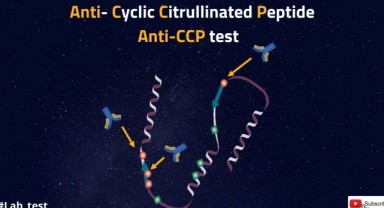

Cyclic Citrullinated Peptide (Ccp) Nedir